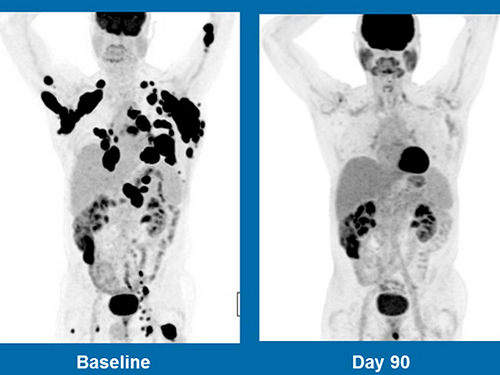

虽然我们的医学在上个世纪中进步很多,但是对于今日世界上最普遍、最具破坏性的疾病,却还没有研发出真正的解药。但是,感谢新研究的出现,这种情形很快就会改变。Kite Pharma ( 风筝制药 )是一家美国制药公司,它刚刚发表极具突破性的研究结果,这个研究是为期半年的基因治疗临床试验:癌症末期病人的病况在单单一轮试验后就完全缓解。

参加这个试验的病人所得的是三种癌当中的非何杰金氏淋巴癌( non-Hodgkin lymphoma)。这些病人的病况如果再恶化,他们剩下的时间就会只有短短数月了。然而,在第一轮基因治疗后、试验开始后第九个月时,有一半的受试病人还活着,而且在他们之中有三分之一的人似乎被完全治愈。

被治愈的人中,有一位四十三岁的病人名叫Dimas Padilla,他来自佛罗里达州的奥兰多。在接受试验之前,化疗已对他的癌症失去效用。在上个八月份,他完成第一轮试验,而且他的癌症现在已经缓解。